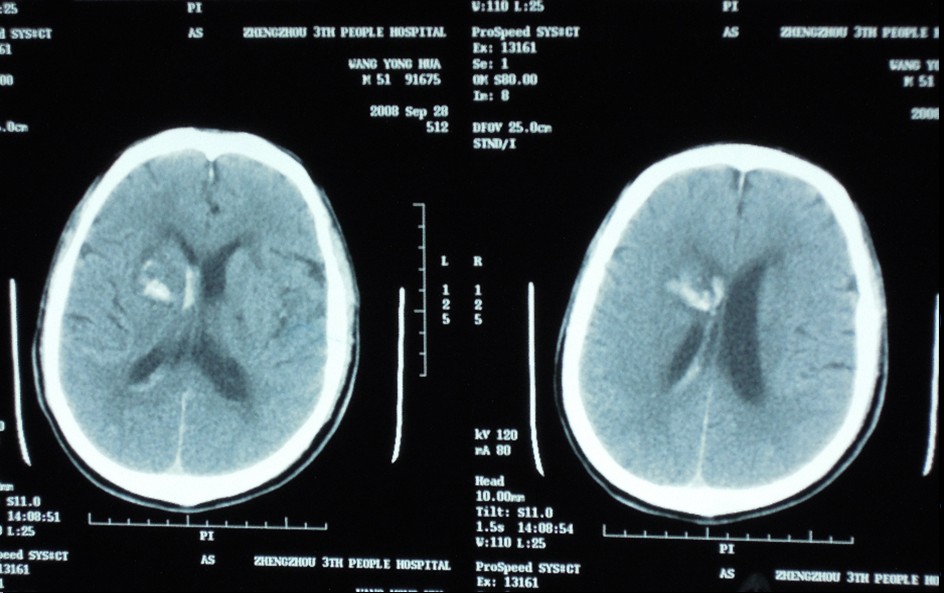

辅助检查:头CT(本院 2011-12-1)双侧侧脑室旁脑梗塞,脑萎缩。

查体:BP160/100mmHg,神志清楚,言语不利,反应迟钝,智能下降,双眼无眼震,左眼不能外展,左侧额纹小时,闭目无力,右侧鼻唇沟浅,伸舌偏左,饮水稍呛咳,双上肢肌力基本正常,双下肢肌力III-IV级,双侧巴氏征、查多克征阴性,双手及右侧面部浅感觉减退。双手抖动明显。考虑进展性脑梗塞。神经介入科医师与患者沟通,为预防病情进一步加重出现闭锁综合症,建议做脑血管介入治疗。家属要求暂用药物治疗,行CTA检查。2小时后右侧鼻唇沟浅,伸舌偏左症状稍减轻,双下肢肌力较前稍好转,肌力IV级。双侧巴氏征、查多克征阴性。头MRI示及头颅CT示预以前对比无变化。